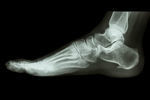

シーバー病・踵骨骨端症

【実例】シーバー病

3ヵ月前から歩く事が出来ない。

1ヵ月後、瑠希亜くんは右かかとの痛みを訴えるようになります。

3日後には歩けない程の痛みとなり、整形外科へリハビリに通います。